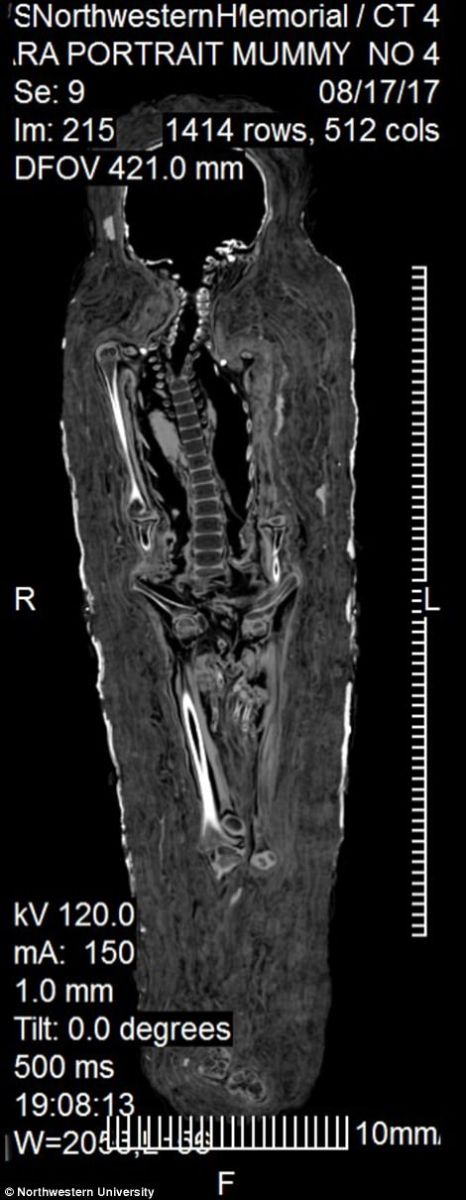

Двухтысячелетняя мумия уникальна тем, что сохранилась нераскрытой с момента обнаружения. Ученые отмечают, что мумии такого рода, с портретом умершего, практически не дошли до наших дней. Чтобы сохранить уникальный артефакт, его исследовали с помощью рентгеноскопии.

Как показали исследования, египетской девочке в момент смерти было около 5 лет — ее рост составлял около 0,9 м, а кости и зубы соответствуют именно этому возрасту.

У тела нет видимых повреждений, из чего сделали вывод, что ребенок умер от болезни.